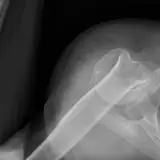

Over 2,100 interactive radiology cases, curated by radiologists for your level of training. Scroll, window, and view cases full screen — just like on PACS. Click linked findings in each writeup to jump straight to them on the image. Cases include sample reports, a focused discussion section, original illustrations, and videos.

Des cas entièrement interactifs avec les outils attendus d'un PACS — défilement, fenêtrage, zoom, déplacement, mesures, ROI et mode plein écran.

Des annotations détaillées mettent en évidence les résultats clés directement sur les cas. Cliquez sur les résultats liés dans les descriptions de cas pour accéder à leur emplacement exact sur l'examen.